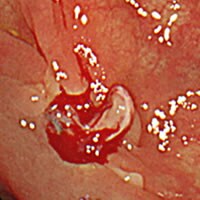

ポリープとは?

ポリープとは粘膜の表面に盛り上がってできるもので、病名ではなく形態を示します。ポリープには良性のものと悪性のものがあり、大腸の場合は良性と言っても悪性化することのない過形成性ポリープと、見つかった時は良性でも、そのまま切除せずに放置することで数年後にがんに変わる可能性のある大腸腺腫があります。大腸腺腫ががんに変わるリスクや時期を予測することはできません。大腸カメラ検査での早期検診、がん化する前の段階でポリープを取り除くことが大切です。

大腸ポリープ(NBI、狭帯光観察と大腸ポリープ切除)

大腸ポリープ切除